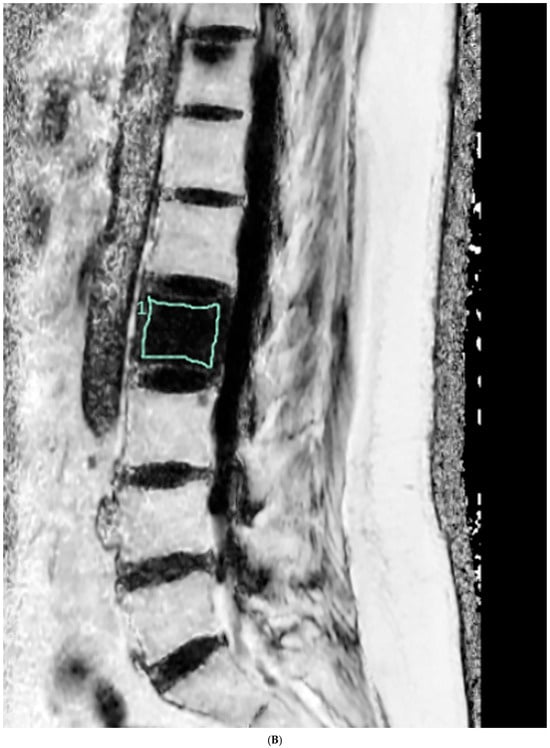

The FF measurement was independently performed by two radiologists who were unaware of the clinical information. Firstly, the FF measurements in GRE-based CSE-MRI were conducted using the INFINITT picture archiving and communication system. Elliptical regions of interest (ROIs) were drawn on the FF map, excluding the posterior venous complex and cortical bone, to encompass cancellous bone as much as possible (Figure 1). ROIs were delineated to the mid-sagittal image. In cases where obtaining information from the central image was challenging, ROIs were drawn on parasagittal images. Measurements were conducted on the L1–L4 bodies, and, in cases where abnormalities invaded all sagittal slices, this level was excluded from the measurements. The median values of the measurements were utilized as representative values (FFGRE). Next, the FF measurement in SE-based CSE-MRI was determined using diffusion analysis software (EXPRESS version 1.0, Philips Healthcare, Seoul, Republic of Korea). This program generates a fat fraction map by simply dividing the signal from the fat-only image by the sum of the signals from the water-only and fat-only images. After creating the FF map using mDixon-XD images, using the same criteria and methodology as in GRE-based CSE-MRI measurements, FF values were obtained from L1–L4 bodies (Figure 1), and the median was used as the representative value (FFSE).

Figure 1.

Lumbar spine MRI of a 59-year-old male. (A) Fat fraction (FF) measurement on gradient-echo (GRE)-based chemical-shift-encoded magnetic resonance imaging (CSE-MRI). The FFGRE in this patient was 66.91%, representing the median value of the L1–L4 vertebral bodies. (B) FF measurement on spin-echo (SE)-based CSE-MRI. The FFSE was 85.84%. The numbers in the figure indicate the ROI numbering in the EXPRESS program. (C) Measurement of the vertebral bone quality (VBQ) score was calculated by dividing the median value of T1-weighted signal of L1–L4 vertebral bodies by the cerebrospinal fluid (CSF) signal at the L3 level. The VBQ score for this patient was 2.63. (D,E) FF color maps were created through GRE- and SE-based CSE-MRI.